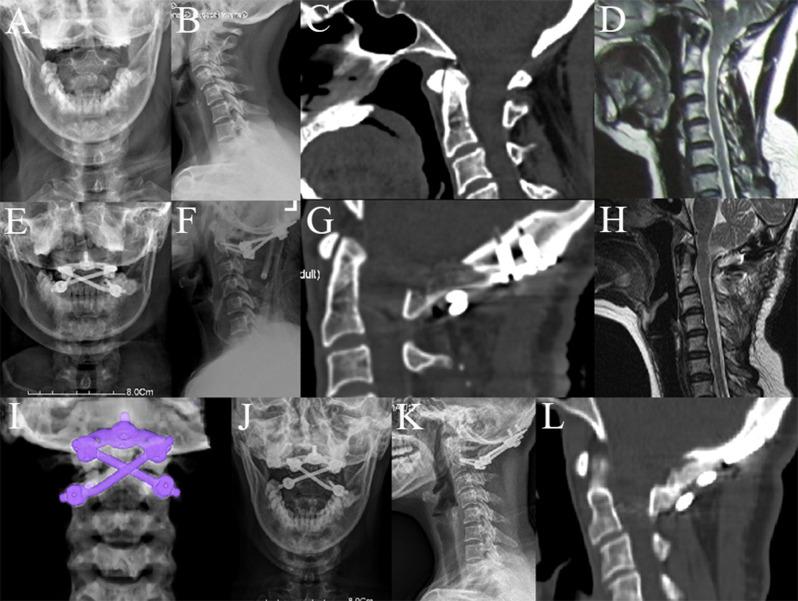

This study is aimed to compare the differences in clinical outcomes between the crossed rod configuration and the parallel rod configuration applied in posterior occipitocervical and atlantoaxial fixations, and to assess the clinical applicability of crossed rods.

METHODS

From January 2015 to December 2021, 21 patients with craniocervical junction disorders were treated surgically with the crossed rod technique (CR group). Meanwhile, 27 corresponding patients treated with the conventional parallel rod technique were included as control (PR group). Clinical data, internal fixation type, neurological status, clinical symptoms relief, image parameter, complications and bone fusion conditions were retrospectively analyzed and evaluated.

No statistically significant differences were found in baseline characteristics, fixation type and postoperative complications between the two groups. Although the postoperative ADI was significantly reduced in both groups, the ADI was significantly greater in the CR group than that in the PR group after surgery and at the final follow-up (P < 0.05). All patients achieved bone fusion at 1-year postoperative follow-up except for one case in the PR group. However, patients in the CR group had a significantly higher fusion rate than those in the PR group at 3 months postoperatively (P < 0.05).

CONCLUSIONS

The application of a crossed rod configuration in posterior occipitocervical and atlantoaxial fixations provides good clinical applicability. Although this technique has a relatively weaker reduction force, it has greater fixation stability and a higher rate of early bone fusion. This technique could be an easy and viable alternative to the current parallel rod configuration for upper cervical surgery.